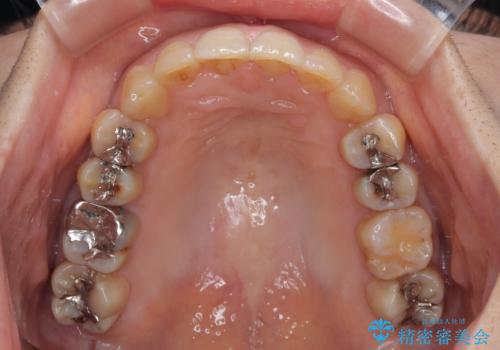

ディープバイトと前歯のデコボコ インビザラインによる矯正治療

- 前歯のディープバイトと叢生を気にして来院された患者様です。

目立ちにくい装置を希望されていたため、ワイヤー装置とインビザラインを提案したところ、インビザラインを希望されました。

下顎大臼歯が手前に倒れていたため、起き上がらせることで咬み合わせ高さを挙上し、ディープバイトと叢生を改善することとしました。

インビザライン特有の奥歯の噛みにくさが治療後半に発言しましたが、無事に終了させることができました。